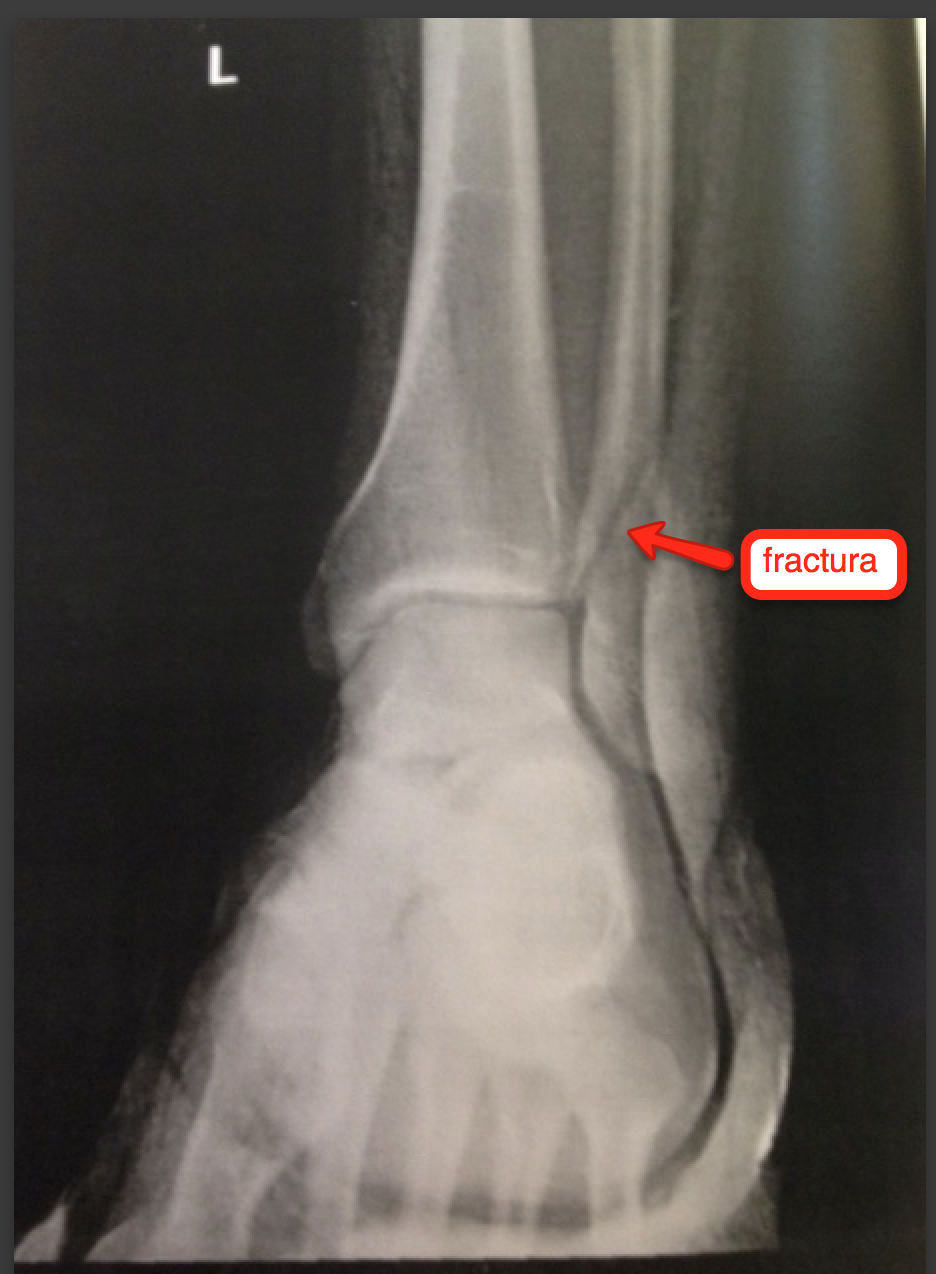

WebFracturas de la cabeza del peroné: Están situadas en el extremo superior del peroné, junto a la rodilla. La consolidación se produce en unos dos meses aunque puede aumentar si. WebSe pueden encontrar signos de lesión del nervio C.P.E. Exploración radiográfica. Proyecciones A-P y Lateral; Confirman el tipo de luxación y el hallazgo de.

WebVisita http://fisioterapia-online.com - Todo sobre fisioterapiaEn este video se plantea la relación de los bloqueos de la cabeza del perone del lado derecho,... WebLas fracturas del peroné distal a menudo resultan en la interrupción de la articulación de la mueca del tobillo, debido al hecho de que el maléolo lateral es importante en la. WebLa lesión del tronco peroneal común produce debilidad para la extensión de los dedos, y extensión y eversión del pie originando caída del mismo y marcha en steppage con.